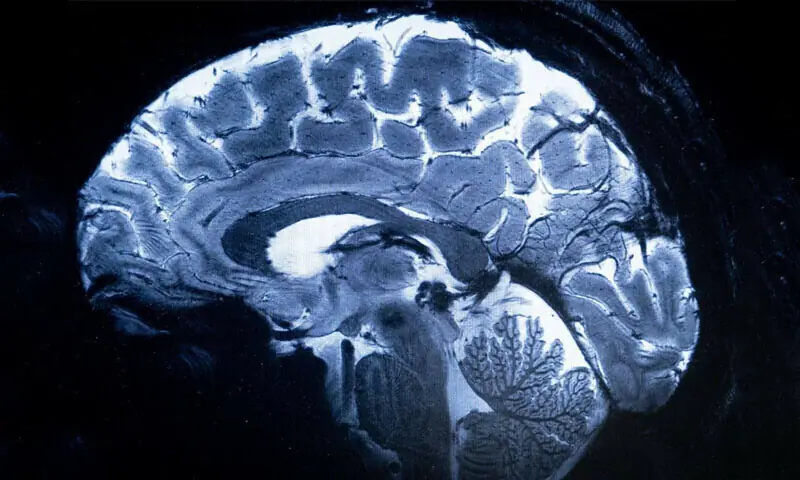

Badanie to opiera się na wcześniejszym badaniu, w którym zespół monitorował aktywność mózgu osób grających w tę samą grę polegającą na dzieleniu się pieniędzmi. Ustalili, że dwa docelowe obszary mózgu – jeden związany z empatią, a drugi z podejmowaniem decyzji – wydają się komunikować, gdy dokonuje się bardziej bezinteresownego wyboru. Celem nowego badania było udowodnienie przyczyny i skutku.

„Nowością są dowody na istnienie przyczyny i skutku” – stwierdziła współautorka Jie Hu z East China Normal University. „Kiedy zmieniliśmy komunikację w określonej sieci mózgowej za pomocą ukierunkowanej, nieinwazyjnej stymulacji, zmieniły się decyzje ludzi dotyczące udostępniania”.